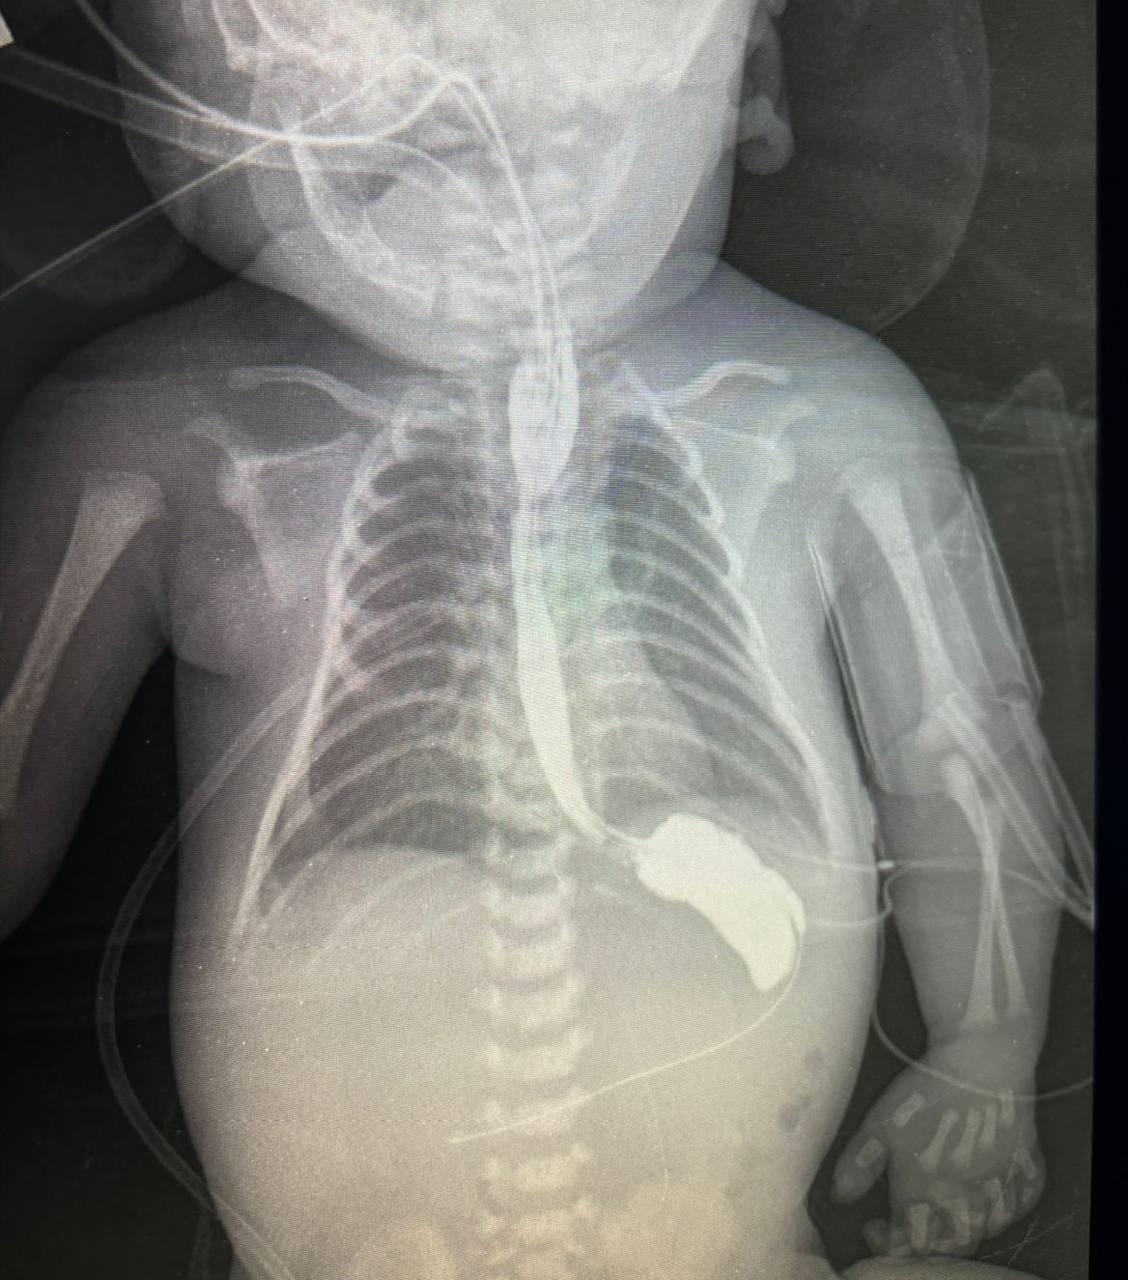

В Московском областном центре охраны материнства и детства городского округа Люберцы спасли новорожденного мальчика с патологией пищевода.

Неполное его развитие не дает возможности кормления ребенка. Но это лишь одна из опасностей заболевания. В большинстве случаев ниже зоны слепого конца пищевода формируется свищ, маленькое соустье, которое соединяет пищевод и трахею. Наличие такого свища опасно постоянным попаданием слюны из пищеварительного тракта в трахею, что быстро приводит к развитию тяжелых форм пневмонии.

«Раньше подобные операции делались открытым доступом, приходилось вскрывать грудную полость, разводя множество мышц и ребра, что впоследствии формировало большую операционную рану и требовало весьма длительный реабилитационный период. В настоящее время мы используем современные методы, которые позволяют проводить операции с минимальным вмешательством и гораздо меньшими травмами для организма»,- отметил заведующий отделением хирургии новорожденных МОЦОМД Михаил Рехвиашвили.